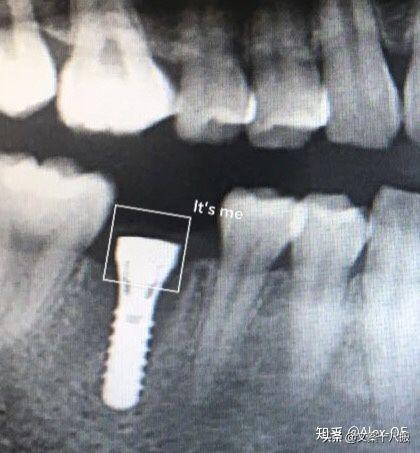

總的來說,步驟有點多但每步都不復(fù)雜,打了麻藥后手術(shù)全程沒什么痛感。選擇了瑞士ITI植體,2018年7月6日下午把種植體,即人造牙根植入了牙槽骨內(nèi),等待愈合三五個月后再匹配牙冠,完成了整個植牙流程。

2018年7月6日,下午先拍了CT,很小劑量的輻射。主任方醫(yī)師說我的情況符合植牙條件,骨量也沒有問題,接下來安排了方案并開始手術(shù),由方醫(yī)師操刀,整個手術(shù)由3個醫(yī)生共同完成。用消毒水漱口兩分鐘后,躺在那個椅子上,燈光刺眼,消毒棉花在口腔周圍一圈一圈得涂,鼻子上都涂了。身上蓋了做手術(shù)的綠布(這個布有名稱嗎?),只露出口腔。因為眼睛也在綠布底下,所以手術(shù)全程看不到醫(yī)生用過哪些工具,只能想象醫(yī)生在干什么,做了麻醉感覺不到切開牙齦,鉆孔的疼痛,但是植入牙體是有感覺的,畢竟那么大的東西硬生生的塞了進(jìn)去,從醫(yī)生手肘的顫動知道這牙題塞進(jìn)牙槽骨挺費勁的。術(shù)前忘記看時間了,估計今天整個過程開始到結(jié)束大概40分鐘,40分鐘內(nèi)還包括了十幾分鐘的醫(yī)生的清潔準(zhǔn)備工作。沒有什么不適,不過醫(yī)生有一會兒手碰巧壓住鼻子上面的綠布了,就只能用嘴呼吸了。我也沒提醒醫(yī)生覺得很快就過去了,醫(yī)生說有任何不適可以隨時叫停。(因為在清潔的綠布底下,隨意抬手示意會造成污染,能不停就別停了,真的有不適吱聲就行)沒告訴他,大概憋了快一分鐘氣覺得種牙還沒有拔牙痛,只是長時間張著嘴比較難受,術(shù)后拍片醫(yī)生說果不錯,配了消炎藥和漱口水,臉貼著冰袋回去了,一周后拆線?,F(xiàn)在已經(jīng)過去8個小時了,麻醉藥也過了,有少量滲血,但疼痛感十分輕微。植牙回去以后,怕麻醉藥過去后疼,下午2點植入后敷冰袋到了晚上8點。那時候確實感覺到疼,不過是輕微而持續(xù)的疼,并且這種輕微的疼大概持續(xù)了四天,術(shù)后配的藥也差不多吃完,那之后就沒事了。

2018年8月15日,距離植入牙根一個多月過去了,現(xiàn)在可以舔到那個缺牙的中間有個硬東西。它像個螺釘,上面有個釘帽,打開這個帽子是內(nèi)螺紋,到時候用來固定牙冠的?,F(xiàn)在是漫長的等待時間,等人造牙根和我的牙槽骨長在一起,醫(yī)生說大概3-5個月后去做牙冠?,F(xiàn)階段要注意牙齒的清潔(哪時候都要,只是現(xiàn)在怕了,特別重視刷牙),從6月開始用上了菲利普的電動牙刷,感覺不錯的,比手動干凈,剛開始震的不習(xí)慣,用久了發(fā)現(xiàn)很舒服。